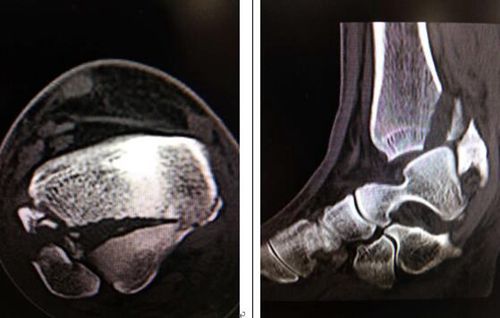

術(shù)前檢查

接診后,足踝科曹廣超主任一邊比劃著一邊用英語與Matteo交流。一番詢問后,曹主任檢查發(fā)現(xiàn),Matteo右腳踝部腫脹、畸形、不能負(fù)重。CT片掃描顯示右脛骨下端粉碎性骨折,是典型的Pilon骨折!而且是比較嚴(yán)重的C3型關(guān)節(jié)面粉碎骨折!